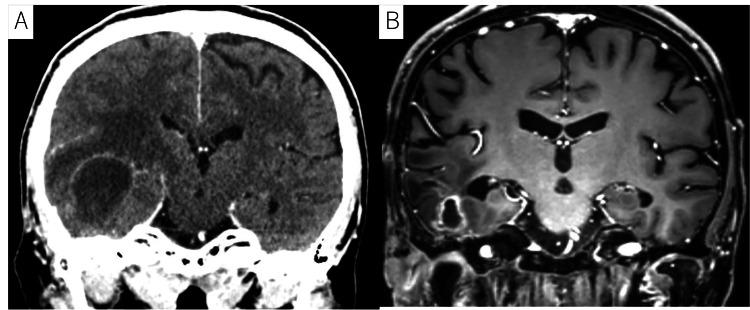

一名65岁女性,有斑块状银屑病和急性呼吸窘迫综合征病史,表现为右外耳道疼痛,被诊断出患有右EACC,EACC充满了右耳道,并侵犯了耳后皮肤、右乙状窦和硬脑膜(图1A、1B)。

图1 A、 B:磁共振成像(MRI)T1加权钆增强图像显示肿瘤(由黄色箭头和红色箭头表示)。此外,图像显示肿瘤侵入右乙状窦和硬脑膜(由红色箭头表示)。根据改良的匹兹堡分类法,该肿瘤被归类为T4。无颈部淋巴结转移或远处转移。C:MRI T2加权图像显示右颞骨破坏,在放射治疗(RT)后七年观察到(由黄色箭头表示)。D:计算机断层扫描(CT)显示右小脑有一个低密度区域的环状增强病变,与放疗后8年出现的小脑脓肿一致。脓肿的最大尺寸为43毫米。通过引流和抗生素治疗进行了治疗。患者没有复发或随后形成脑脓肿